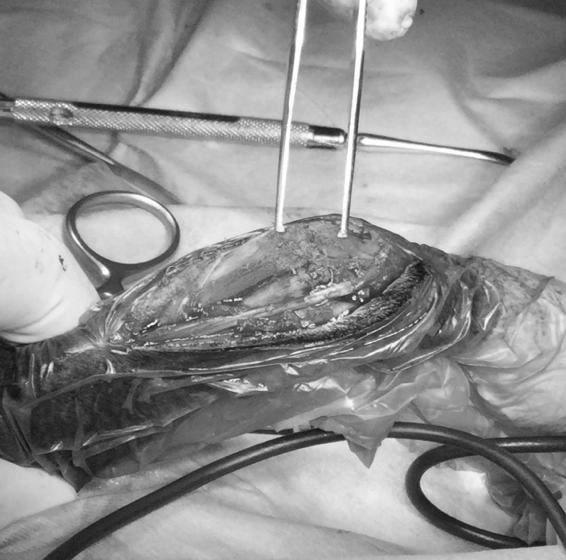

症例3:キルシュナーワイヤーのピンニングによる整復

ペルシャ猫 11ヶ月齢 雄

他院にて左大腿骨遠位の成長板骨折(salter-harrisⅠ型)が認められており、治療相談を目的として来院。当院にて、キルシュナーワイヤーを用いたピンニングにより骨折部位の整復を行いました。術後の経過は良好で、現在も経過観察中です。

Arthrex社のターゲティングデバイスを用いてピンニングの位置を調整することで、確実な固定を行っています。当院ではこの手術器具以外にも、人の手術にも使用される様々な器具を導入し、手術精度を高め、また医療メーカーと新しい器具の開発、試作にも取り組んでおります。